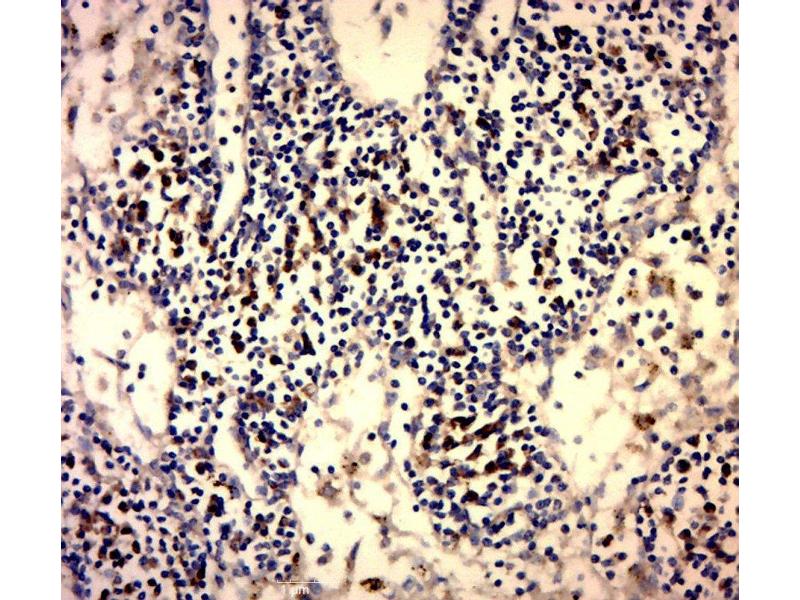

• Immunohistochemistry (IHC)

• Immunohistochemistry (Paraffin-embedded Sections) (IHC (p))

• Immunohistochemistry (Formalin-fixed Sections) (IHC (f))

• Immunohistochemistry (Fixed) (IHC (fx))